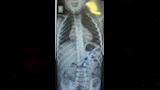

نجح فريق طبي من وحدة أمراض الجهاز الهضمي والكبد ومناظير الأطفال بقسم طب الأطفال بمستشفى سوهاج الجامعي، في إجراء تدخل دقيق لاستخراج دبوس من معدة طفل يبلغ من العمر أربع سنوات، بإستخدام منظار معدة خاص بالأطفال، دون حدوث أي مضاعفات، وغادر الطفل المستشفى بعد ثلاث ساعات فقط من الإجراء، وهو في حالة صحية جيدة.

وأكد الدكتور أحمد كمال، المدير التنفيذي للمستشفيات الجامعية، أن التعامل مع الحالة تم بسرعة وكفاءة، حيث تمكن الفريق الطبي من استخدام المنظار الخاص بالأطفال لاستخراج الدبوس دون أي تدخل جراحي، مما ساهم في خروج الطفل من المستشفى في نفس اليوم بحالة ممتازة.